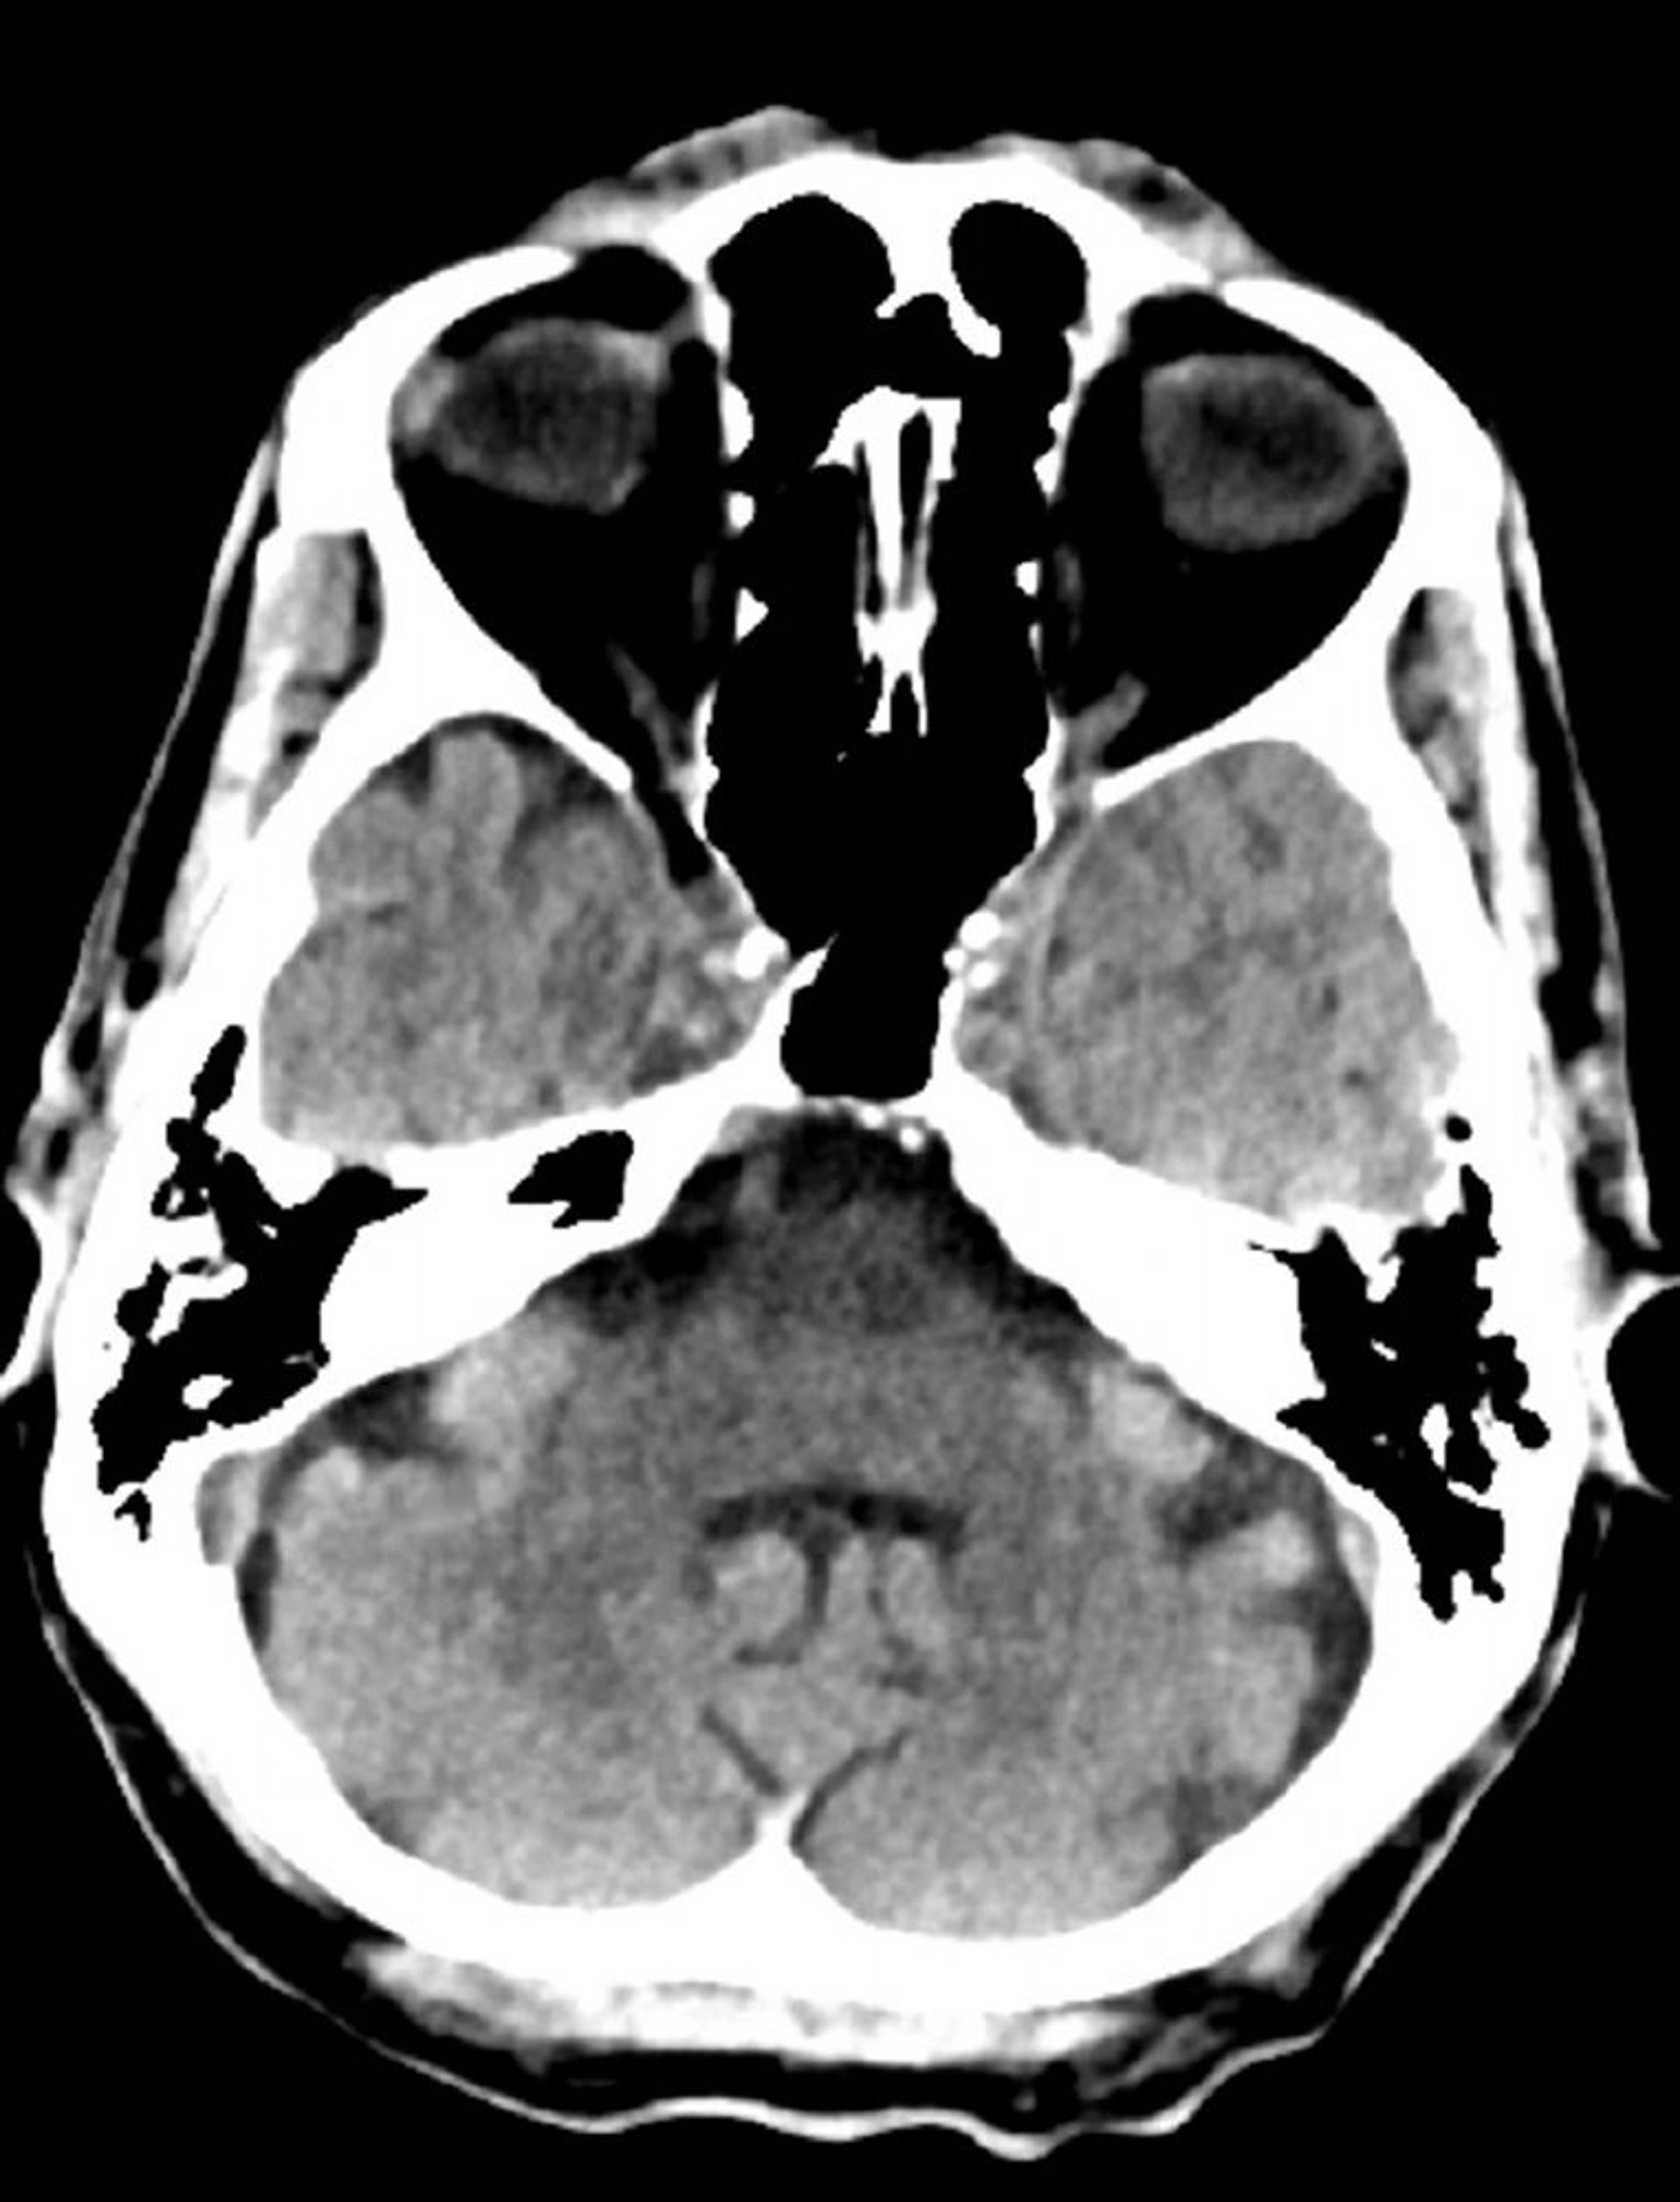

TC cerebrale normale (adulto di 74 anni), slide 8

Questa immagine è una normale TC della testa di un adulto di 74 anni. Rispetto alla normale TC della testa di un soggetto di 30 anni, i ventricoli e i solchi sono più grandi. Questi reperti sono normali in questa fascia d'età.